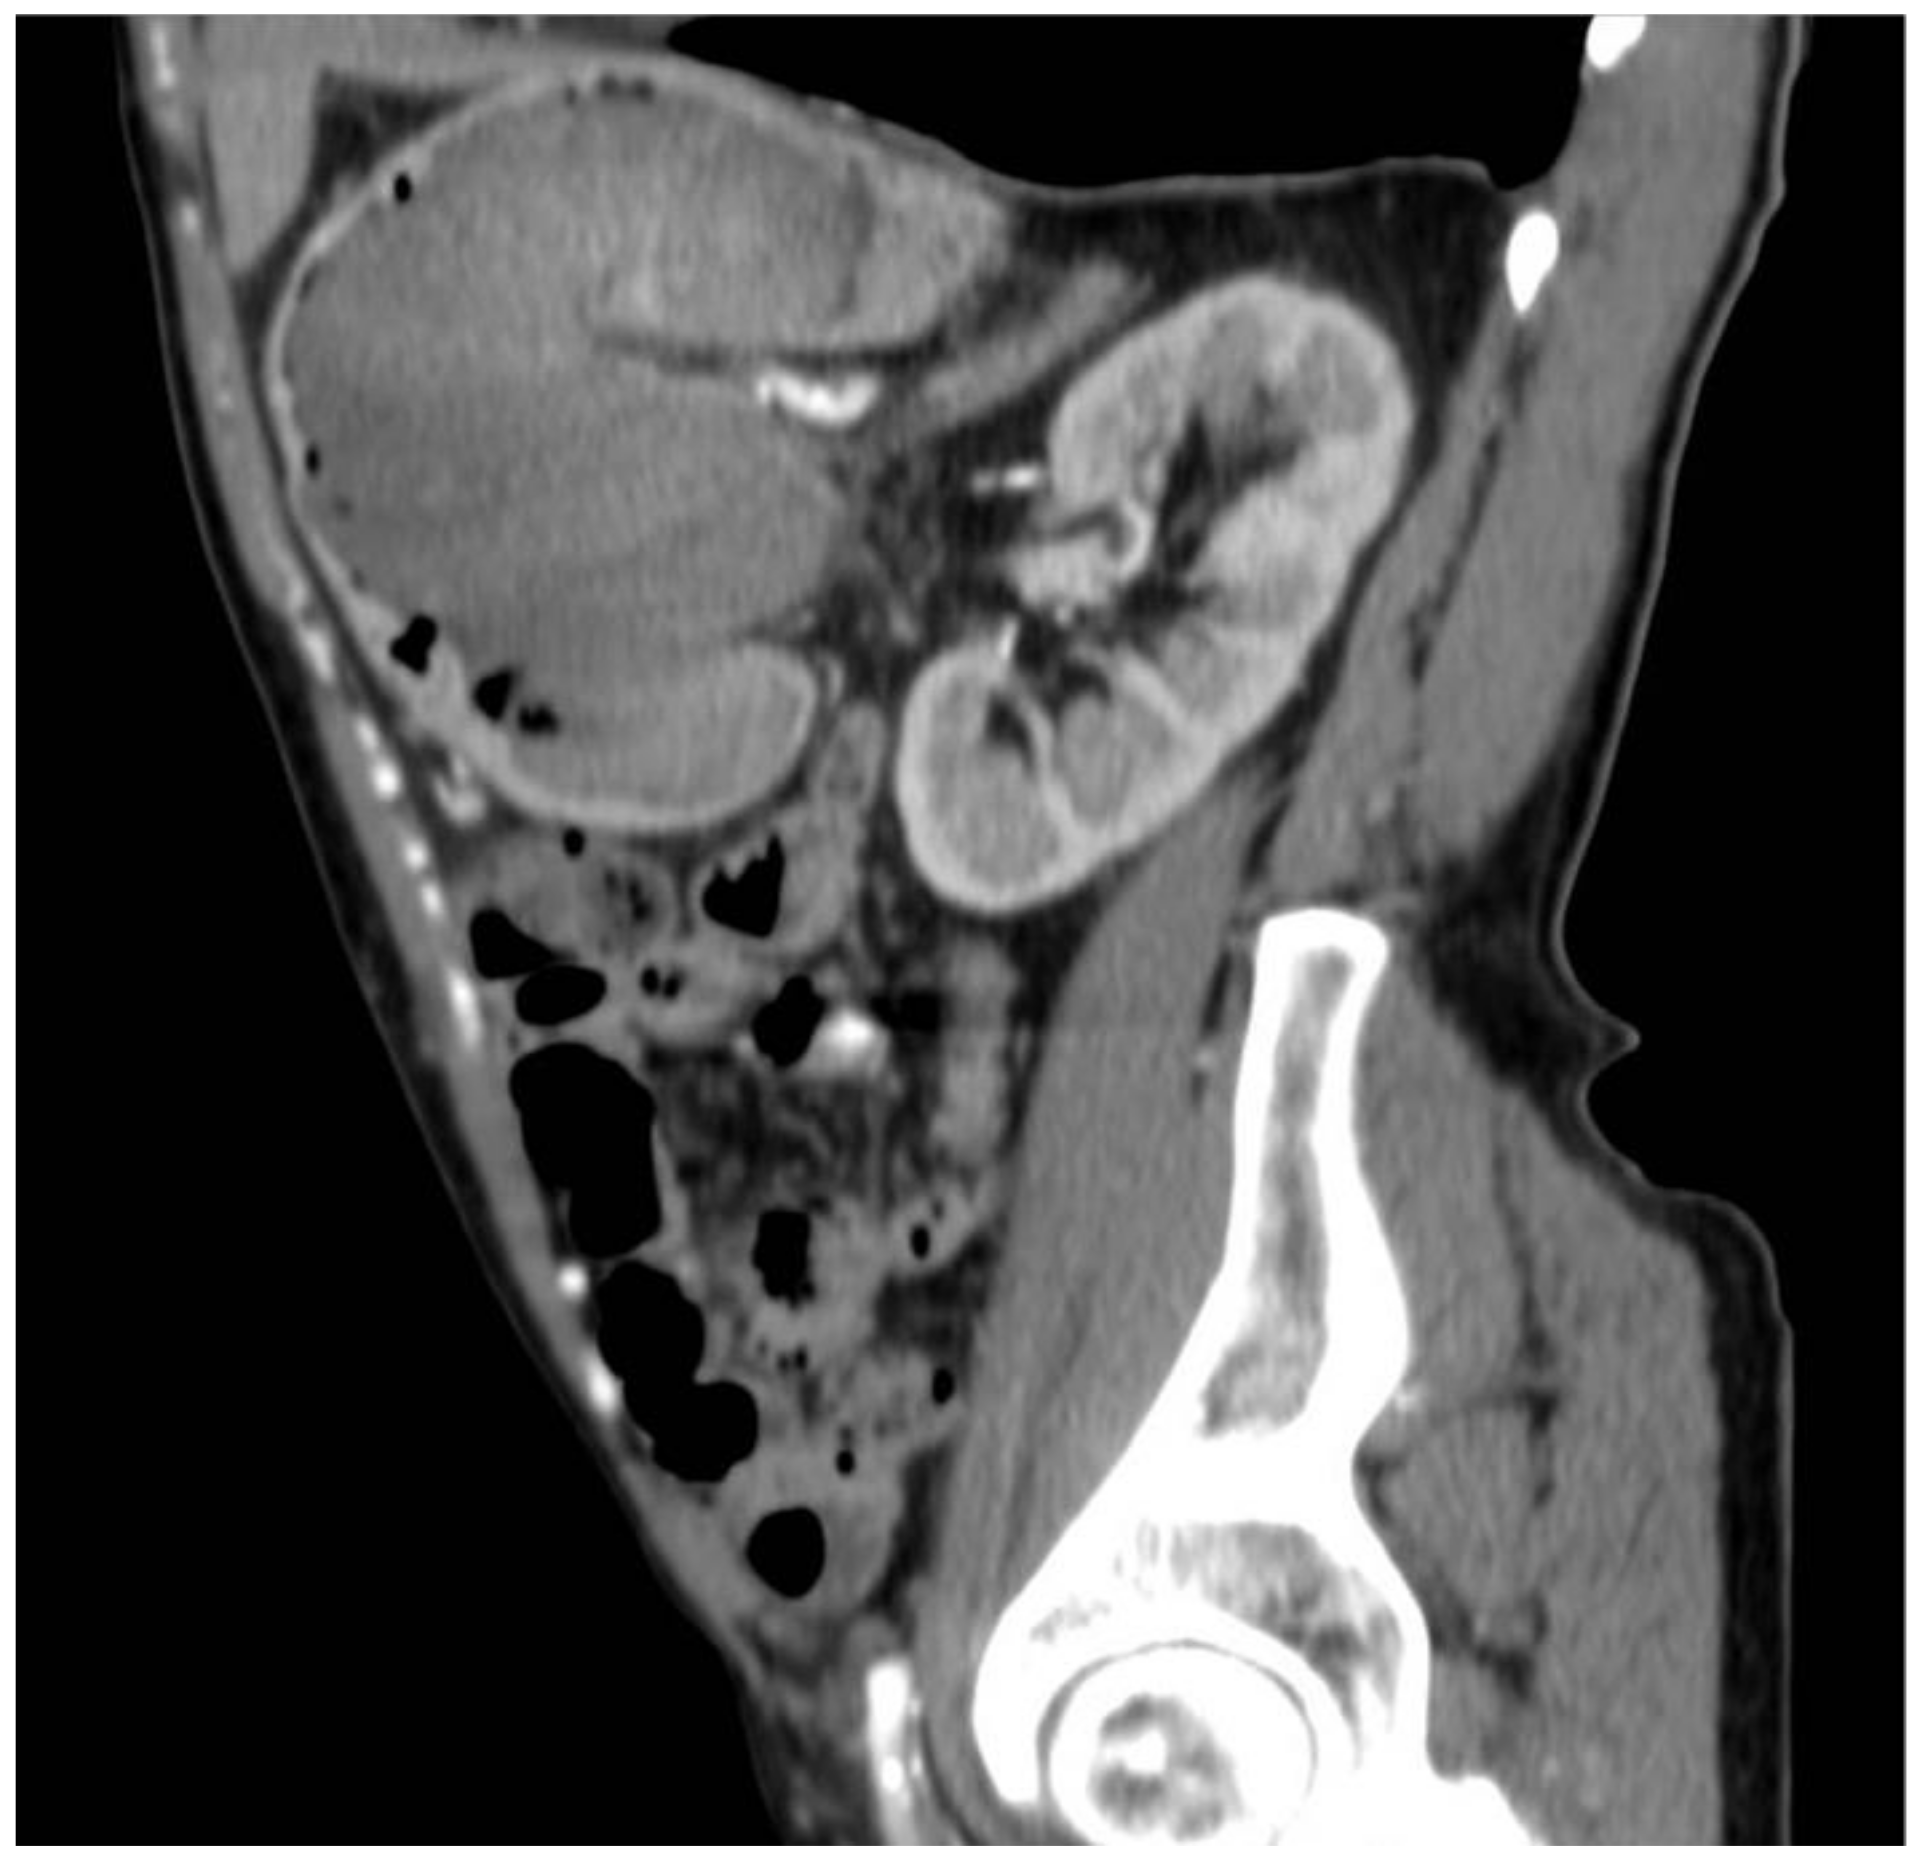

2. Case Report